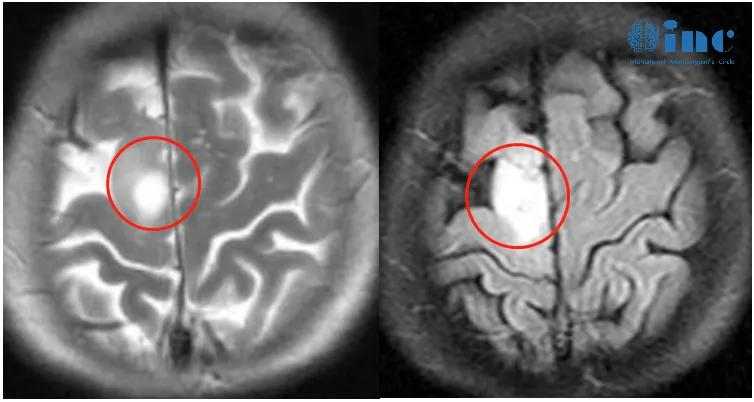

2023年1月底罗女士突然左腿失去知觉摔倒,后面又类似情况发生几次。3月份,他们来到当地医院进行检查,颅脑MR+增强显示:右侧额叶异常信号灶,考虑低级别胶质瘤。

“这个肿瘤与我去年在独墅湖医院最后一天做手术的病人的肿瘤非常相似(几乎一样)。这是一个明确的手术指征,就像我们去年12月初做的那样,使用术中磁共振对比。手术的主要风险是左腿的运动功能障碍,但我认为这基本不会发生。在术后早期阶段,只可能出现暂时性的腿部无力,但无论出现这种情况,将逐渐恢复正常。”

巴教授评估意见表示肿瘤位于右侧中央前-失状窦旁区,没有浸润到中央脑回。这意味着我们实际上可以切除肿瘤,而不会造成新的运动功能障碍。

4月,INC德国巴特朗菲教授为额叶胶质瘤合并癫痫发作患者——66岁的罗女士顺利行肿瘤切除,在术中导航、术中核磁、术中神经电生理监测下,肿瘤取出的同时也保护了大脑正常功能。

手术后病理结果为低级别胶质瘤。